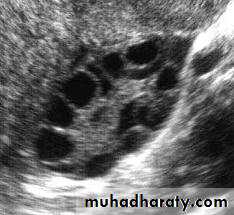

(3) Mature (graafian) follicles

1.reaches a diameter of 20-30 mm or more prior to ovulation,2.large enough to protrude from the surface of the ovary and be detected by ultrasound imaging.

Polycyctic ovary syndrome